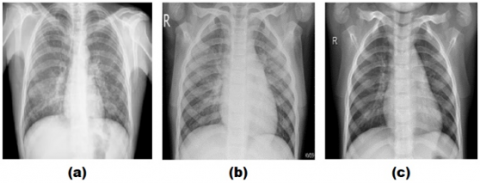

This study used a curated CXR (chest X-ray) dataset that was collected and prepared by Sait et al. [13]. The dataset consists of 3 classes, namely: CXR infected with COVID-19, CXR infected with pneumonia and normal CXR without any infection. The data totals 9208 CXR images, divided into 1281 CXR COVID-19, 4657 CXR pneumonia and 3270 normal CXR. Examples of CXR images of COVID-19, pneumonia and normal data can be seen in Figure 1.

Figure 1. Example of a CXR image: (a) COVID-19; (b) Pneumonia and (c) Normal